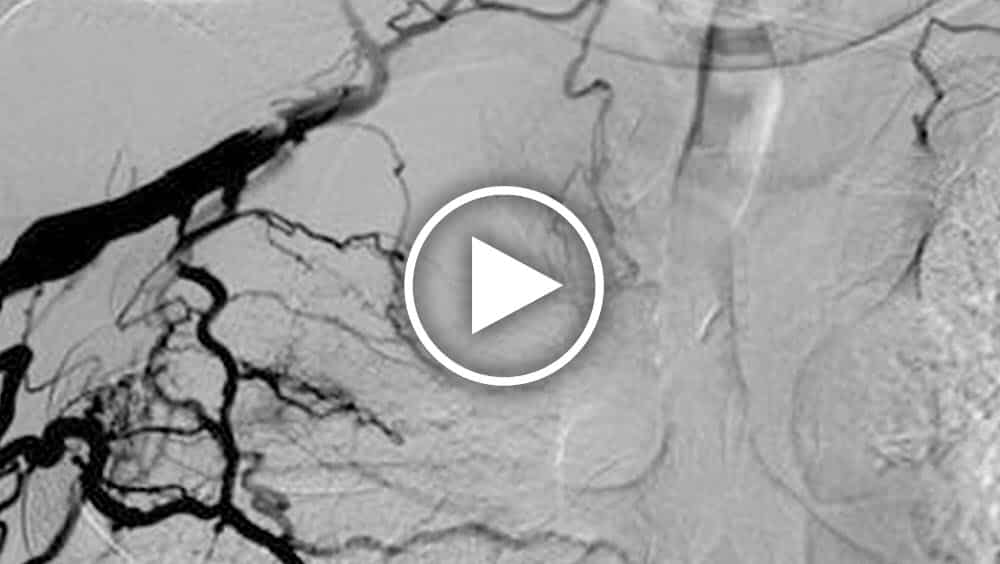

Bilaterale zentrale Venographie苏珥Bestatigung静脉zentralvenosen Stenose